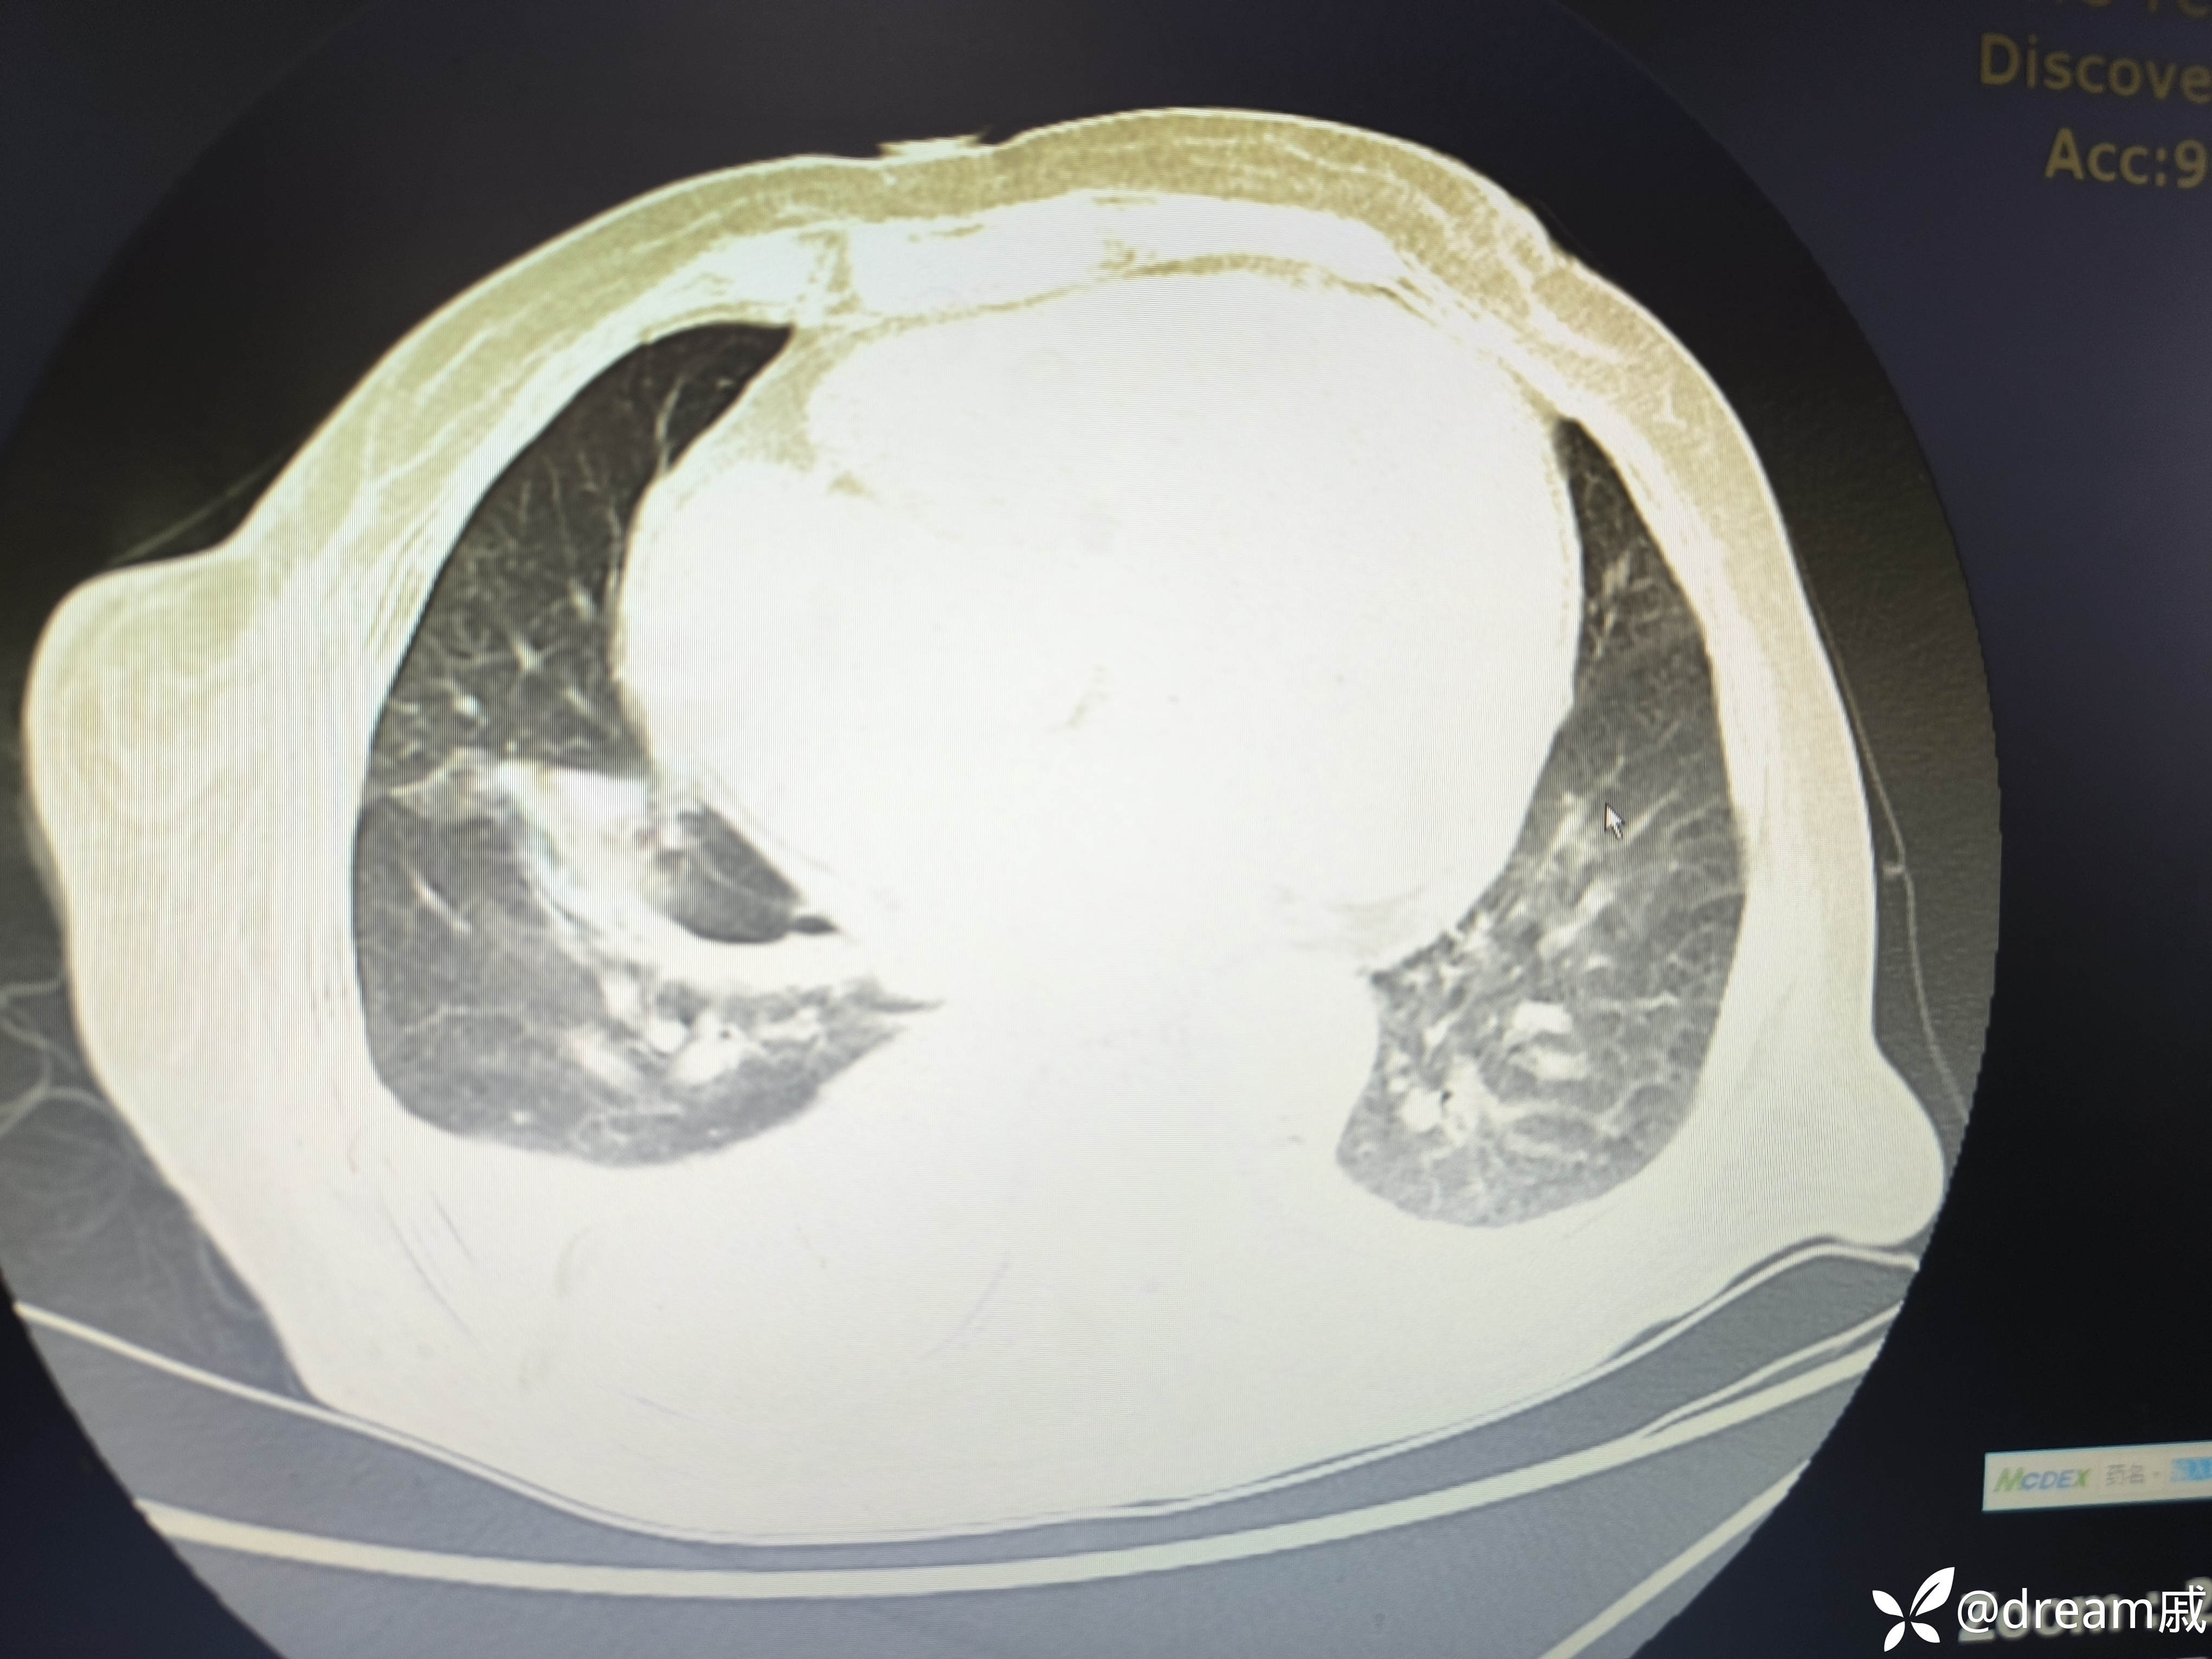

胸部CT示右肺中下叶斑片影,双肺局部间质性改变。

5月27日复查CT如下